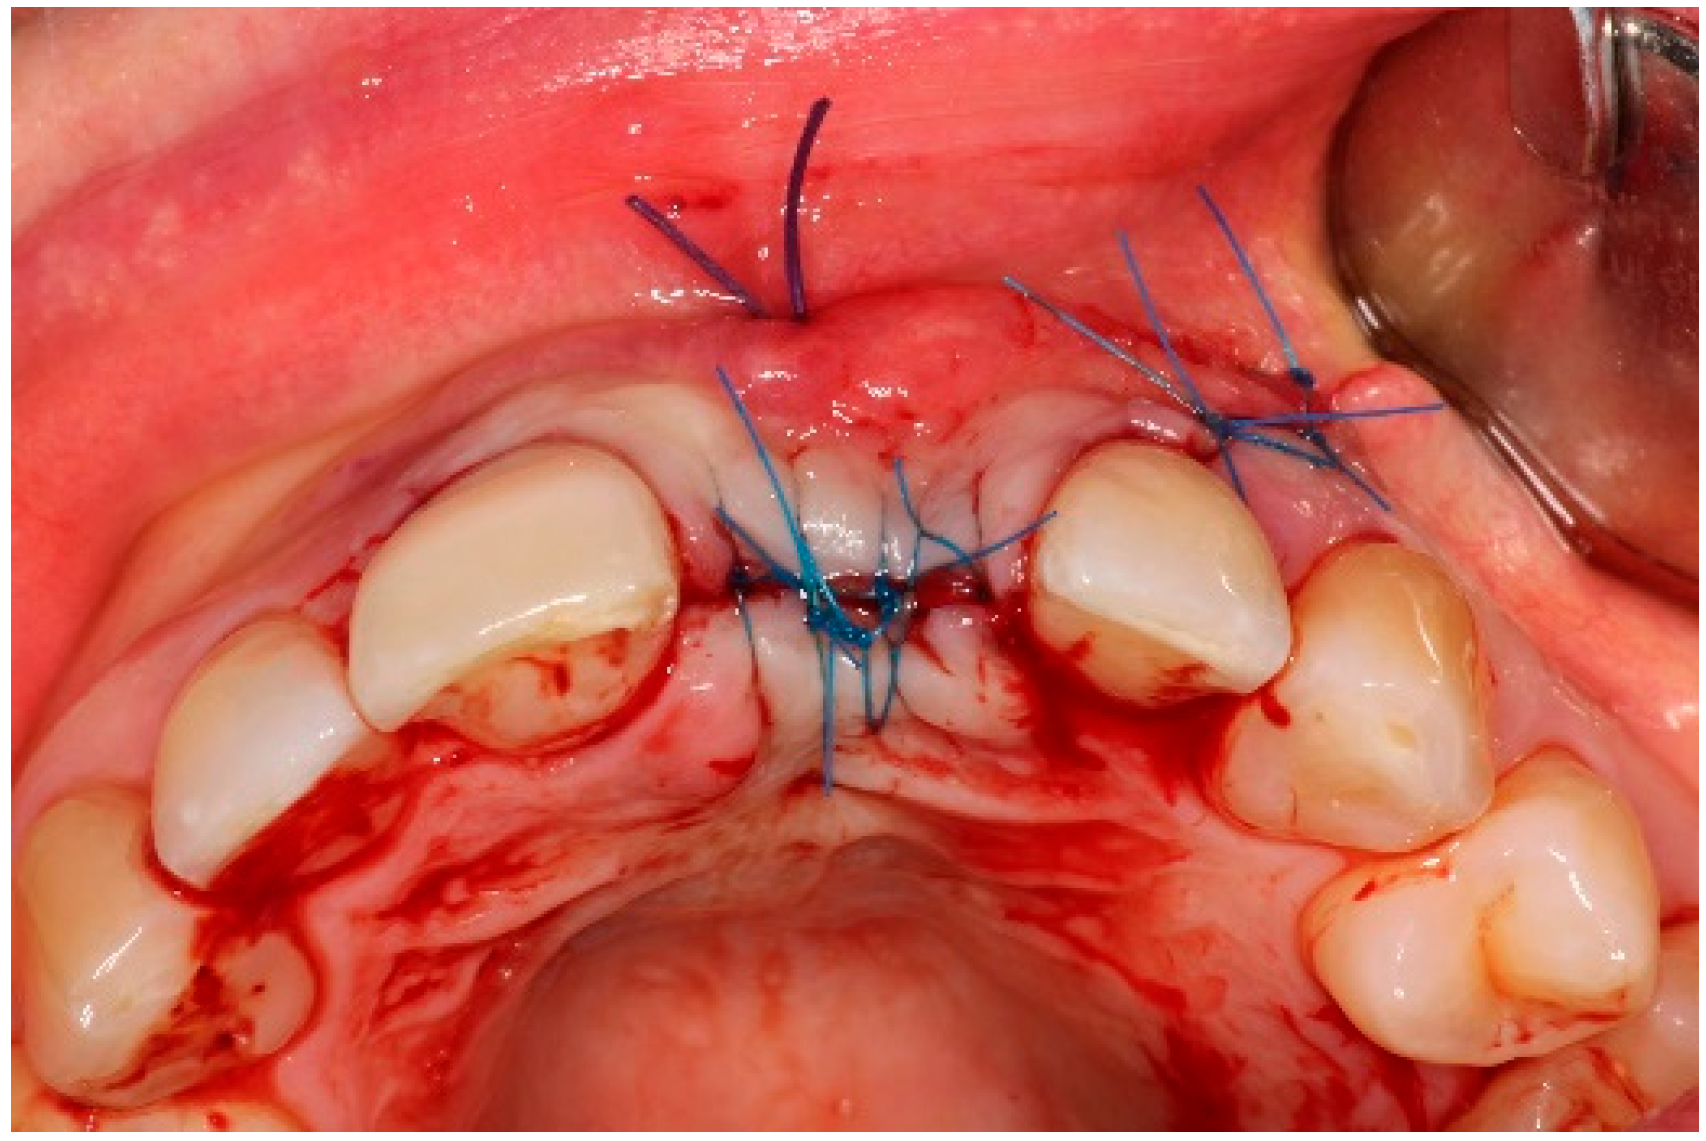

4. Timeline and Diagnostic Assessment

5. Therapeutic Intervention

5.3. Surgical Treatment